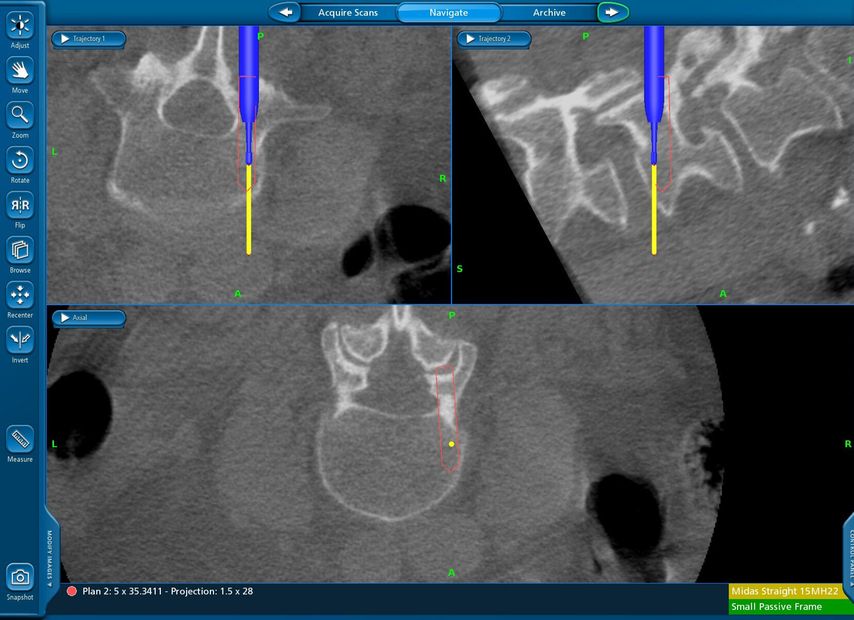

Fallbeispiel 1

Beispiel für die Implantation zervikaler Pedikelschrauben. In diesem Fall kam es bei einem 61-jährigen Patienten 10 Jahre nach anteriorer zervikaler Diskektomie und Fusion (ACDF) C4/5 und ventraler Verplattung C4–6 zu einer Ankylosierung auch von C6/7. Nach Sturz kam es zu einer Fraktur bei C6/7 mit begleitender Bogenfraktur und auch Beteiligung der dorsalen Ligamenta (Abb. 1 und 2). Klinisch bestanden ausgeprägte Nackenschmerzen und kein neurologisches Defizit. Es wurde die Indikation der dorsalen Verschraubung von C4 auf Th1 gestellt. Intraoperativ wurde routinemäßig zusätzlich eine kleine Referenzschraube in einer Lamina – entfernt von der Dornfortsatz-Referenzklemme für die Navigation – gesetzt. Mit dieser konnte intraoperativ die Genauigkeit der Navigation exakt überprüft werden (Abb. 4 und 5). Mittels navigierter High-Speed-Fräse wurden die Schraubenkanäle vorgebohrt (Abb. 6), im Anschluss wurde der Bohrkanal ausgetastet und die Schrauben wurden implantiert. Abbildung 7 zeigt eine Röntgenkontrolle 3 Monate postoperativ.

Abb. 4: Screenshot der Navigationssoftware intraoperativ (Stealth Station S7). Es erfolgt die intraoperative Verifizierung der Navigationsgenauigkeit mittels kleiner Schraube in der Lamina, positioniert idealerweise entfernt von der Dornfortsatz-Referenzklemme. Die navigierte Fräse wird im Situs exakt auf die Schraubenmitte gerichtet, und die Navigation bestätigt die Genauigkeit | |